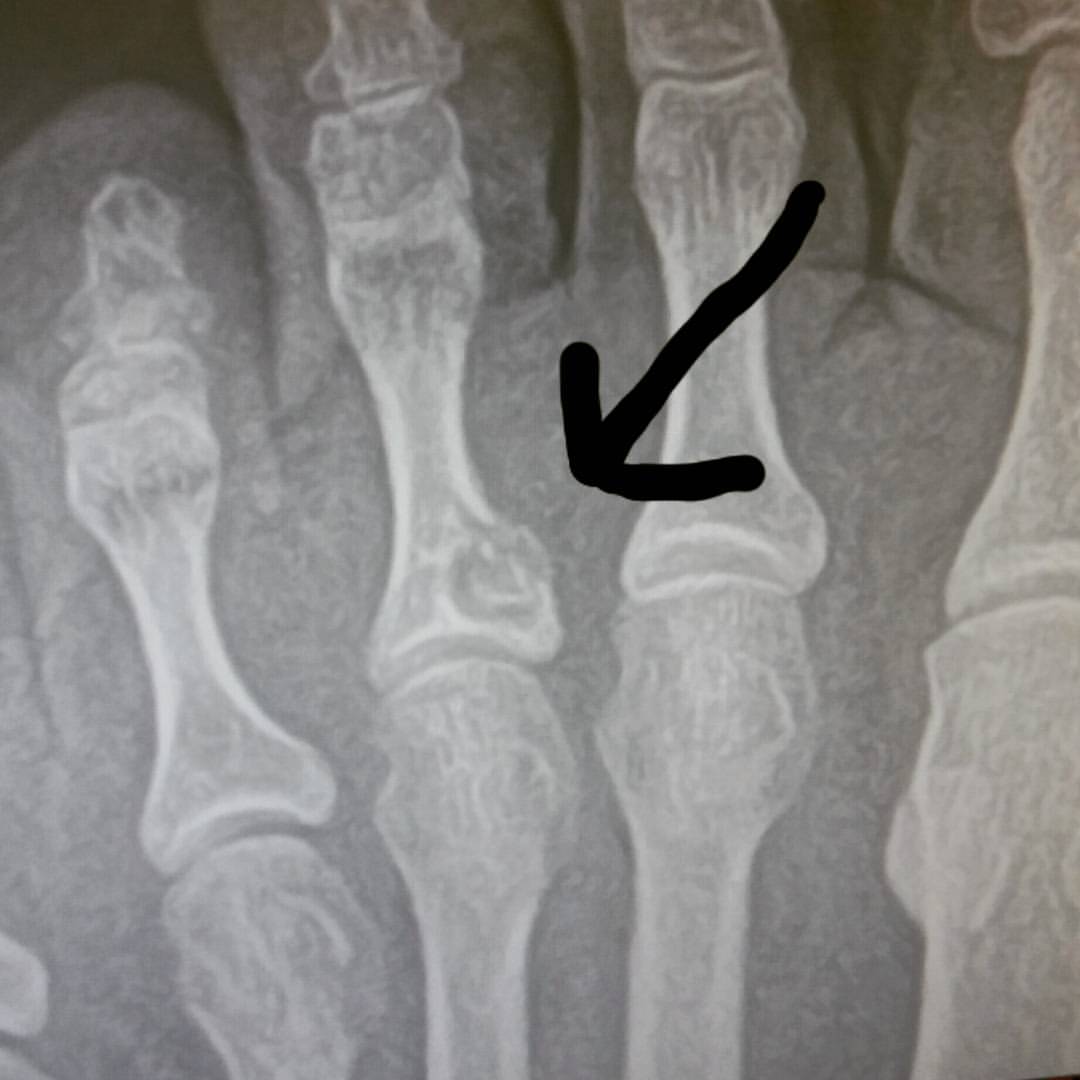

![]() |

| That left foot was broken. The right wasn’t working. This was not my best performance on the field. |

| See that? That’s a broken foot. After healing 3 weeks. |